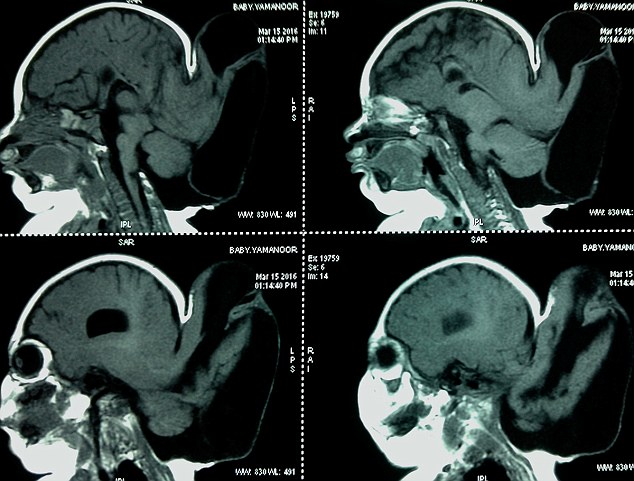

Daily Mail đưa tin cho biết bé Yamanoor Naranal (5 tháng tuổi) được chuẩn đoán mắc hội chứng thoát vị màng não chẩm.

Đây là một trong những loại dị tật hiếm gặp khiến dịch tủy não tràn ra ngoài hộp sọ và tạo thành khối u. Nếu khối u phát triển to và vỡ ra sẽ gây nguy hiểm đến tính mạng.

Theo chia sẻ của tiến sĩ Hariprakash, người trực tiếp tiến hành phẫu thuật cho bé cho biết ca phẫu thuật này rất khó khăn và tỷ lệ thành công khá thấp "Nếu như không may mấy khoảng 10ml máu cũng có thể cướp đi tính mạng của bé".